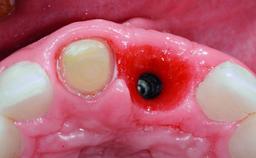

Replacement of a Compromised Upper Right Central Incisor: Hard- and Soft-tissue Augmentation, Late Placement of an RC Bone Level Implant

Bone Augmentation Horizontal|Simultaneous|Staged

Augmentation Materials Xenogenous|Membrane

Placement Protocol Early or late implant placement

Bone Volume Deficient horizontally, requiring prior grafting